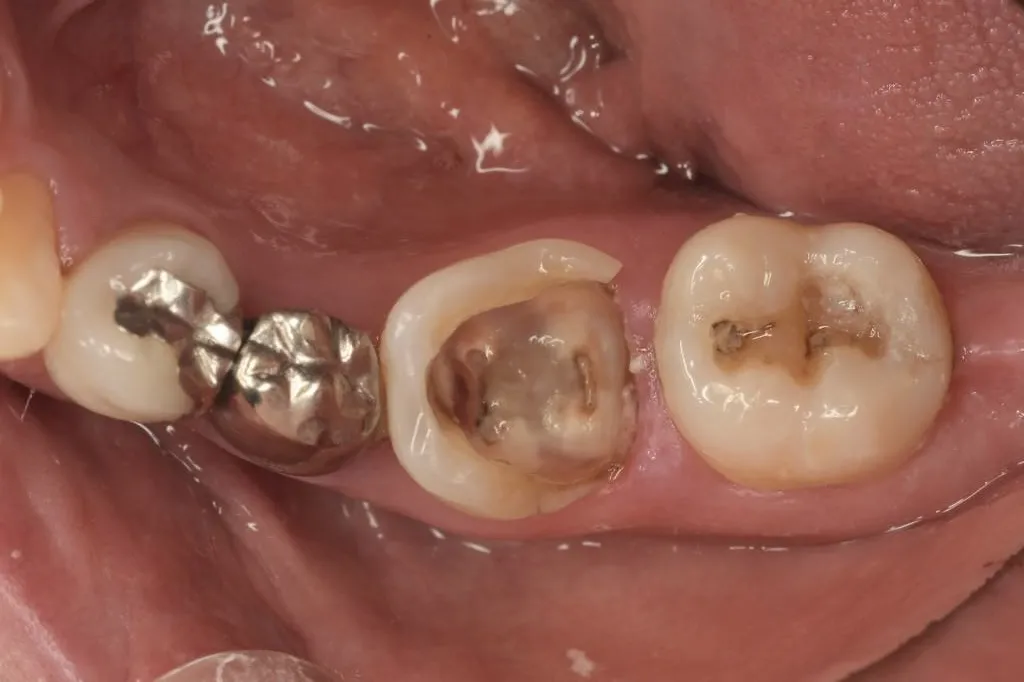

インプラント治療症例①

インプラント治療症例②

インプラント治療症例③

インプラント治療症例④

インプラント治療症例⑤

インプラント治療症例⑥

歯周病などで骨が少なくなった患者さんに対して行う、骨を再生させる処置(ソケットプリザベーション)